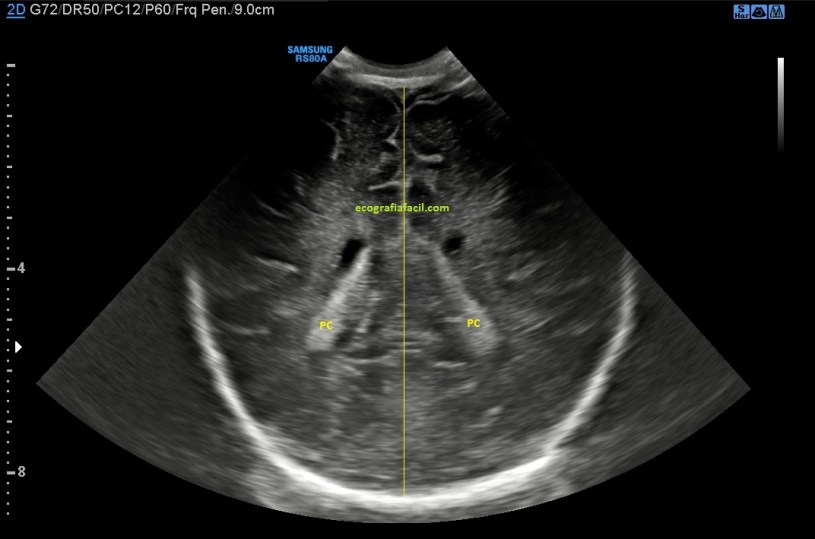

Asociado a esta masa, descendiendo por el canal inguinal, en la búsqueda del teste, encontramos un área donde unas estructuras tubulares y tortuosas de aspecto anecoico y móvil muy compatibles con varicocele, que ya hemos estudiado en el blog con anterioridad y compatibles con venas varicosas…

…con la aplicación del doppler color y la maniobra de valsalva confirmamos dicha sospecha para que el radiólogo tenga constancia del hallazgo. Marcamos siempre la maniobra, y colocamos siempre correctamente el pictograma como indica la flecha amarilla, recuerda que no solo la calidad de imagen debe ser el objetivo. El TSID trabaja para un radiólogo que revisará la imagen eco-anatómica y toda la información que nosotros podamos ofrecerle al margen usando textos y/o pictogramas en el contexto siempre de un protocolo como el que estoy contándote hoy.